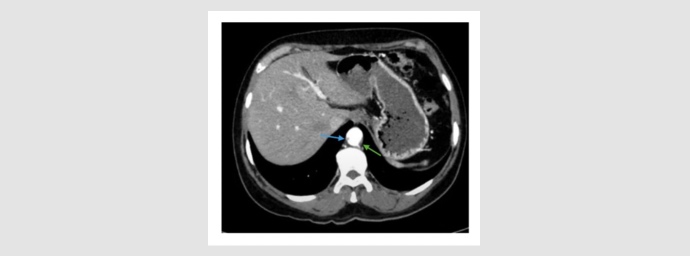

Tomografía de tórax. La flecha verde indica la presencia de una lesión con densidad de tejido blando ubicada en el cuadrante inferolateral de la mama derecha, de aproximadamente 15 mm de tamaño.